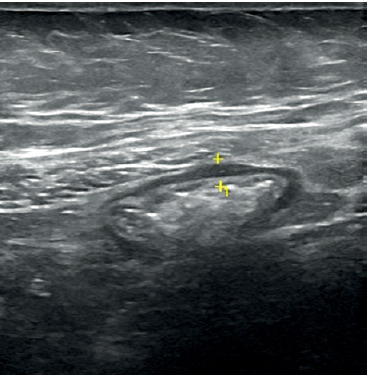

Aim: Our objective was to evaluate the role of a combination of both intestinal ultrasound (IUS) and colour Doppler with different parameters for monitoring changes in inflammation over time and to reveal their potential role in the assessment of response to biologic therapy in inflammatory bowel disease (IBD) patients.

Material and methods: Before the induction of biological therapy, IUS together with colour Doppler of the intestine was conducted. Response to therapy was defined following the international guidelines.

Results: A total of 45 patients with histopathological diagnosis of IBD were enrolled in the study. All patients received biological therapy and were assessed for response after 3 months. Out of those patients, 34 (75.6%) had good response while 11 (24.4%) failed to respond to the treatment. Our findings point to a strong association between bowel wall thickening (BWT) and serum albumin, erythrocyte sedimentation rate (ESR), and c-reactive protein (CRP). The overall sensitivity of IUS varied from 54 to 93% when evaluating bowel affection, with a specificity of 97-100%, in comparison to our results, which showed a sensitivity of 64-74% and specificity of 79-82%. Doppler parameters could predict the response to the biologic therapy in IBD patients.

Conclusions: Intestinal ultrasound and colour Doppler provide a safe, non-invasive way to monitor changes in inflammation and blood flow in the digestive tract.